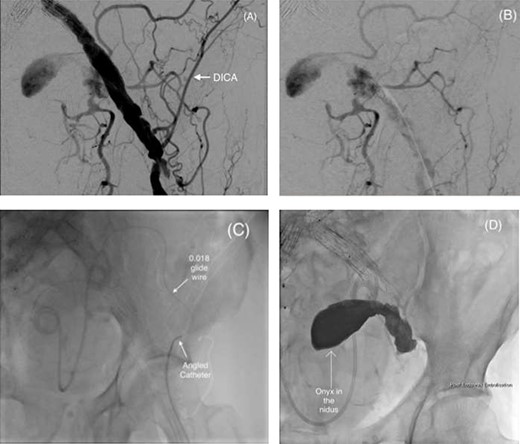

The IIAA feeding vessels were traced to retrograde flow from the deep branches of the pelvis. An anastomosis from the left deep circumflex iliac artery (DCIA) was mapped as an access vessel to the IIAA. Under local anaesthesia, retrograde transarterial access was achieved through the left common femoral artery with a 5Fr prelude (Merit Medical Systems, Inc, UT, USA) sheath under ultrasound guidance. An angled Van Schie 2 catheter (Cook Medical, Inc) and 0.018 Glidewire® (Terumo; Somerset, New Jersey, USA) were used to access the left DCIA and a Progreat® 2.4Fr microcatheter (Terumo; Somerset, New Jersey, USA) used to cannulate the aneurysmal sac.

A 21-ml total volume mixture of low and high viscosity ethylene-vinyl alcohol copolymer (EVOH), Onyx™ LES 18 and 34 respectively, was used for the successful embolization of the nidus (Fig. 3A–C). Completion angiogram demonstrated no further perfusion of the IIAA, and the patient was discharged home the same day. A follow-up of 90-day imaging demonstrated continued IIAA occlusion, with no sac expansion.

(A and B) Pre-embolization digital subtraction angiography (DSA) via a retrograde ipsilateral common femoral artery puncture demonstrating the left IIAA with inflow from the deep pelvic arteries including the DICA. (C) Microcatheter utilization to cannulate the aneurysm nidus with an angled catheter over an 0.018 hydrophilic Glidewire® to access the DICA. (D) Onyx™ successfully injected into the IIAA nidus.